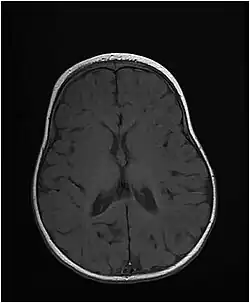

Axial T1-weighted MRI of the brain at 10 months old showing under-myelination of the internal capsules, relative under-myelination of the remainder of the subcortical white matter, and a thin corpus callosum. From an MTHFS deficiency case report by Romero et al., 2019.[1]

The disease starts at birth or in early infancy and presents with microcephaly, short stature, and developmental delay. Patients develop seizures that may be hard to control. Brain imaging shows delayed myelination and hypomyelination.[2] Mutations of the MTHFS gene disrupt folate metabolism, which is very important for the proper development of the nervous system and myelination of nerve fibers.[2]